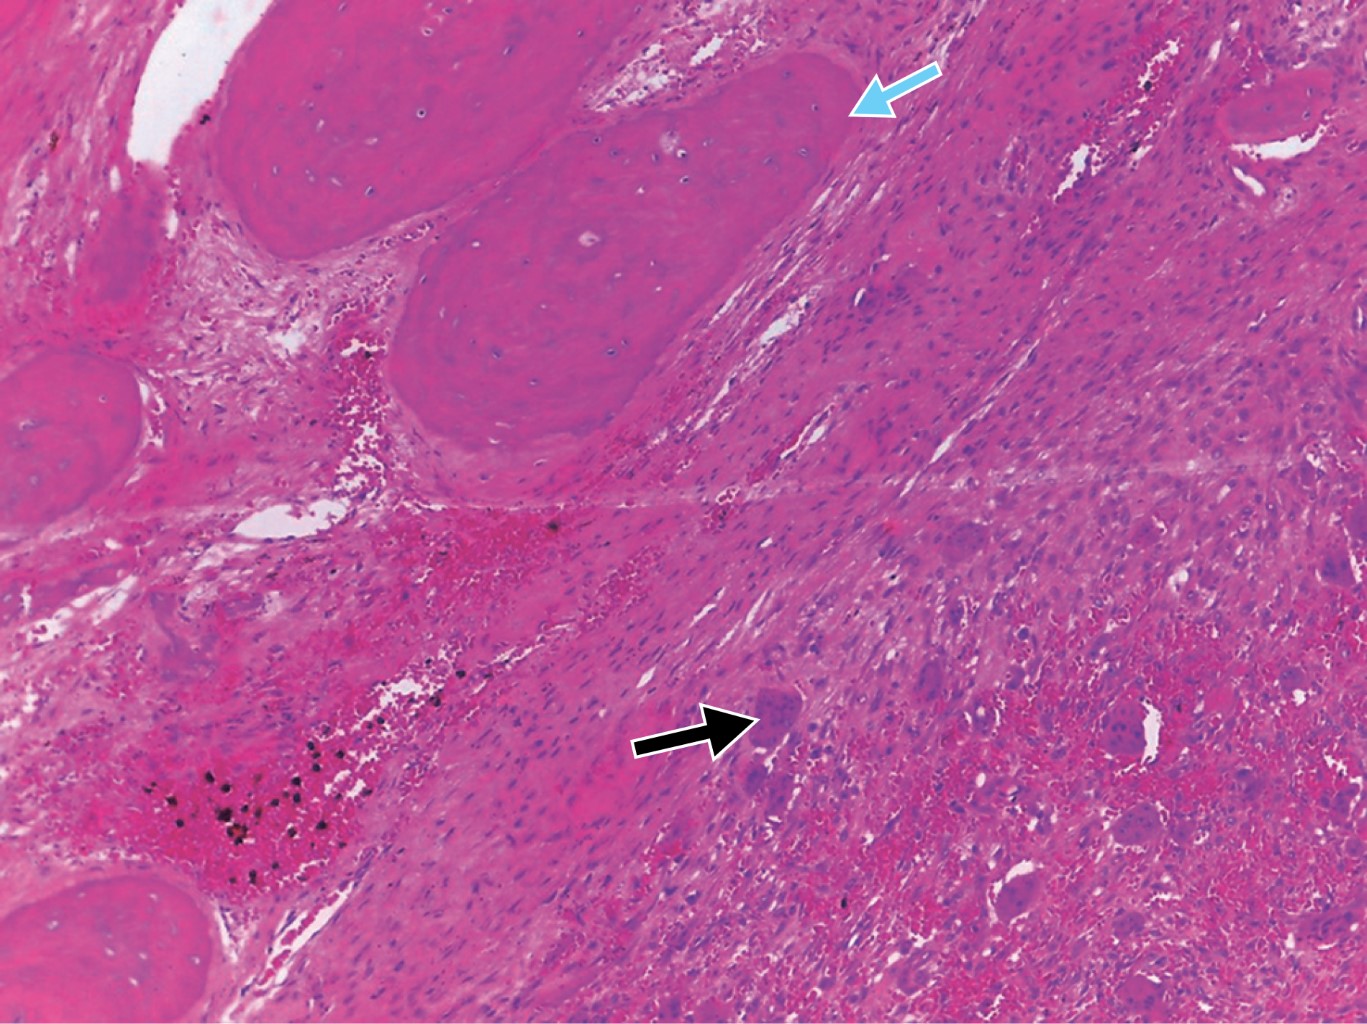

Las lesiones híbridas se consideran una patología rara que presenta elementos de diferentes entidades, cada una de las cuales tiene una categoría tumoral. En la actualidad hay menos de diez casos notificados de lesiones híbridas que muestran la asociación de una lesión central de células gigantes y un fibroma osificante. Dado que un protocolo de tratamiento para este tipo de patologías no está bien establecido en la literatura, presentamos un caso de manejo integral, incluyendo la rehabilitación, basado en la revisión de la literatura. Se trata de una paciente de 31 años con un diagnóstico inicial de lesión central de células gigantes en el cuerpo mandibular izquierdo, que fue tratada con triamcinolona intralesional, sin encontrar respuesta tras seis semanas de tratamiento, por lo que decidimos realizar una resección en bloque de la lesión y la reconstrucción simultánea con un injerto libre de cresta ilíaca anterior, obteniendo un resultado histopatológico definitivo de lesión híbrida (lesión central de células gigantes más fibroma osificante), posteriormente se realizó una rehabilitación protésica implantosoportada. En los casos de lesiones híbridas, consideramos que el manejo quirúrgico es adecuado, dado el comportamiento particular de dicha entidad que no responde adecuadamente al manejo farmacológico, recomendamos evitar el uso de medicamentos antirresortivos ya que perjudicaría el resultado de un tratamiento quirúrgico y reconstructivo posterior.

Figura 3